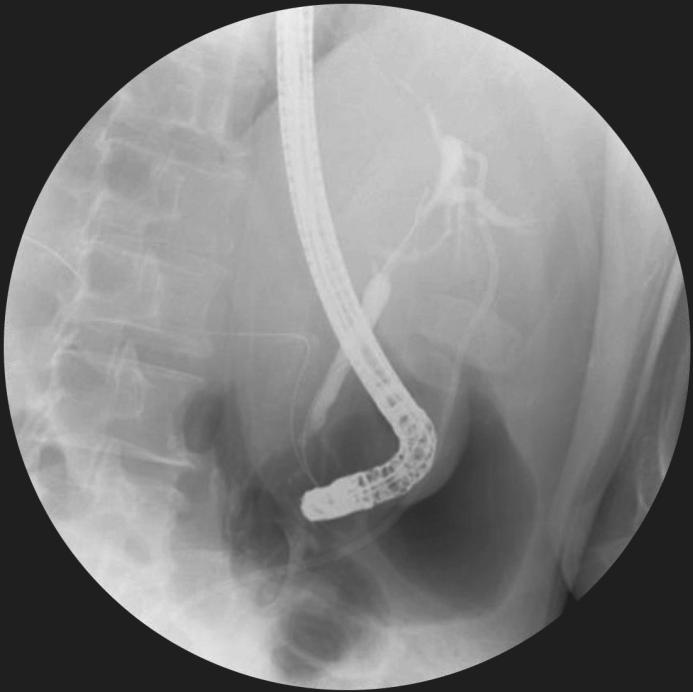

(4)括约肌切开术:无论SEMS在胆道内还是跨乳头置入,都不一定行胆道括约肌切开术,是否进行乳头括约肌切开的主要依据是能否顺利插管(图2)。

图2 胆囊癌致肝门部胆管狭窄行ERCP置入支架,切开奥迪括约肌